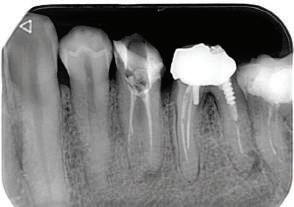

орални снимки и снимки на позата, пал пация на мускулите, брукс-чекър, оклу зограми, кондилография, рентгеногра фии, СВСТ и ядрено-магнитен резонанс на темпоромандибуларните стави). Преди началото на ортодонтското лечение всички стари възстановява ния бяха свалени и бяха заменени с дъл госрочни временни от хибридна керами ка. На девитализираните зъби бе прове дено ендодонтско релечение. Индивиду ализиран оклузален сплинт бе направен с цел да се постигне контролирано репо зициониране на долната челюст, като носенето му продължи три месеца до възстановяване на правилната позиция на ставния диск и затихване на орофаци алната болка и дискомфорт в ставата. Брекетите в горната челюст бяха за лепени, за да започне подреждането и нивелирането на зъбите, докато паци ентът все още носеше сплинта. След края на терапията със сплинта бе на правена кондилография, за да се потвър ди триизмерната позиция на долната челюст. След залепване на брекетите в долна

Dental Tribune Bulgarian Edition / октомври 2022 г. 17клиничен случай с алайнери леко струпване в долната че люст; несъответствие по Болтън (мандибуларен излишък от 3.06 мм във фронталната зона и общо 1.47 мм); издължено лице с лицева аси метрия; конвексен профил с ретруди рана долна челюст и проми нентен нос. На мястото на зъб #46 бе на лице имплант, а зъби #16 и 26 са ендодонтски лекувани. Тези зъби бяха асимптоматич ни, затова бе взето решение да се прави релечение само при нужда. Мъдреците липсваха. Анализът на телерентгеногра фията (фиг. 4) показа ретрог натна мандибула (SNB: 74.2°) и нормална инклинация на резците както в

Dental Tribune Bulgarian Edition / октомври 2022 г.18 воначалния план. Тези пробле ми бяха адресирани чрез допъл нителна поръчка на алайнери с торк контрол и зададено екст рудиране на задните зъби с цел установяване на добри оклузал ни контакти в дисталните об ласти, като бяха предвидени и оптимизирани атачмънти с контрол над корените за корекция на ангулацията на макси ларните резци (фиг. 8). Резултати от лечението Панорамната рентгено графия след ортодонтското лечение показа благоприятна паралелна позиция на съседни те зъби, подходяща за поставя не на имплант в областта на #22, както и конвергенция на ко рените на зъби #44 и 45 (фиг. 9), но преценихме, че няма да от деляме допълнително лечебно време за коригирането ѝ поради факта, че пациентката бе мно го доволна от постигнатия до момента резултат. След при ключване на лечението бяха постигнати отлични взаимо отношения клас I при мола рите и канините, а срединни

Dental Tribune Bulgarian Edition / октомври 2022 г.22 клиничен случай | ортодонтия 14-и месец В горната и долната челюст са поставени последни стоманени дъга с омега луп и тай бек – 17 x 25 SS с четвъртито сечение. Назначени е ластик за средната линия в комбинация с клас 3 ластик (1/4”, 6 1/2 oz). Контролни рентгенографии 13-и месец Екстракционните пространства са затворени. Направена е контролна панорамна снимка за оценка позицията на корените. Взето е решение за презалепване на брекетите на 12, 22 и пръстените на 36 и 46. 21-ви месец Средната линия в горната и долната челюст съвпадат. Ластиците са спрени. Свалени са пръстените и брекетите в горната и долната челюст, зигзаг ластици не са използвани поради благоприятните оклузални взаимоотношения. Фиг. 11j Ортопантомография в края на лечението. Фиг. 11k Телерентгенография след края на лечението. Фиг. 11l Анализ на телерентгенографията след лечението. Фиг. 11m Последователност на дъгите в горната и долната челюст Фиг. 11n Суперимпозиция на PreOp и PostOp ортопантомографии. 10-и месец Затварянето на пространствата е предвидимо и контролирано, без да се отварят пространства в зъбната дъга. Фиг. 8a Фиг. 8b Фиг. 8c Фиг. 8d Фиг. 8e Фиг. 10a Фиг. 10b Фиг. 10c Фиг. 10d Фиг. 10e Фиг. 9a Фиг. 9b Фиг. 9c Фиг. 9d Фиг. 9e Фиг. 9f Фиг. 11a Фиг. 11f Фиг. 11j Фиг. 11l Фиг. 11m Фиг. 11n Фиг. 11k Фиг. 11g Фиг. 11h Фиг. 11i Фиг. 11b Фиг. 11c Фиг. 11d Фиг. 11e